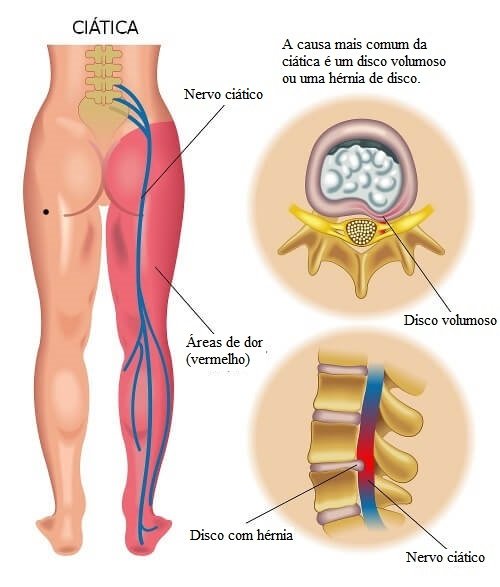

2. Ciática

A ciática é outra das causas mais frequentes. Nesse caso, o desconforto se expande em direção à região das nádegas e continua em direção às pernas de uma maneira muito mais pronunciada do que na tensão muscular. Os sintomas que acompanham essa dor são:

- Adormecimento na parte inferior das costas.

- Sensação de queimação devido ao excesso de calor desde as costas até as pernas.

- Dificuldade para realizar qualquer movimento, mas, sobretudo, ao se sentar.

O ciático é o maior nervo dos nervos do corpo e tem muitas terminações que começam na coluna vertebral. Por isso, quando há dor, isso pode ser limitante. Vale destacar que as pessoas mais vulneráveis a esse tipo de doença são aquelas com 50 anos de idade ou mais.